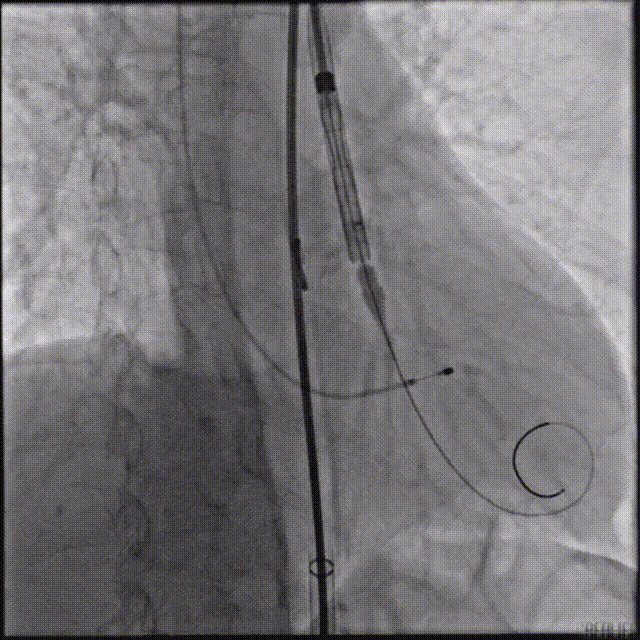

主动脉根部造影,采用20mm球囊预扩,有明显腰征,无造影剂渗漏。

主动脉根部造影

球囊预扩